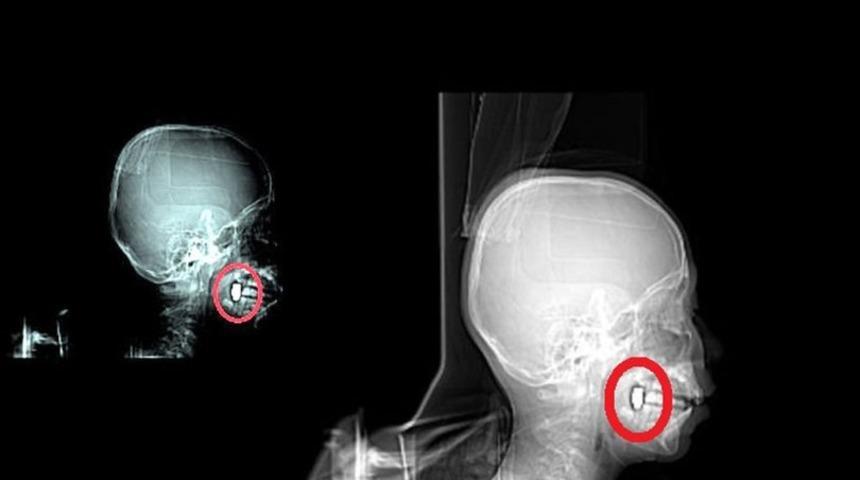

Osman Gündüz, sabaha karşı kusmaya başladı. Bunun üzerine ailesi Osman’ı Kadınhanı Devlet Hastanesi’ne götürdü. Osman Gündüz, buradan da Konya Numune Hastanesi’ne sevk edildi. Gündüz’ün burada çekilen tomografisinde başından giren mermi çekirdeğinin çenesine saplandığı belirlendi. Gündüz buradan da Selçuk Üniversitesi Tıp Fakültesi’ne gönderildi. 4 gün yoğun bakımda kaldıktan sonra normal odaya alınan Osman Gündüz’ün çenesindeki mermi çekirdeği sağlığı acısından şu an için çıkartılmadı. Gündüz’ün bir süre çenesindeki mermi ile yaşamını sürdüreceği belirtildi.

Bayram Gündüz, hastanede yapılan tetkiklerde oğlunun başına mermi isabet ettiğini öğrenince şaşırdıklarını belirtti. Mermi girdikten sonra başında herhangi bir kanama olmadığını ifade eden Gündüz, çenesine saplanan mermi çekirdeğinin, şu an için çıkartılmadığını ve oğlunun bir süre mermi çekirdeğiyle yaşayacağını söyledi. Oğlunun sağlık durumunun iyi olduğunu ifade eden Gündüz, ”4 gün yoğun bakımda kaldıktan sonra şu an normal odaya alındı. Tedavisi sürüyor. Sağlığı iyi durumda; ancak yürümekte güçlük çekiyor” diye konuştu.